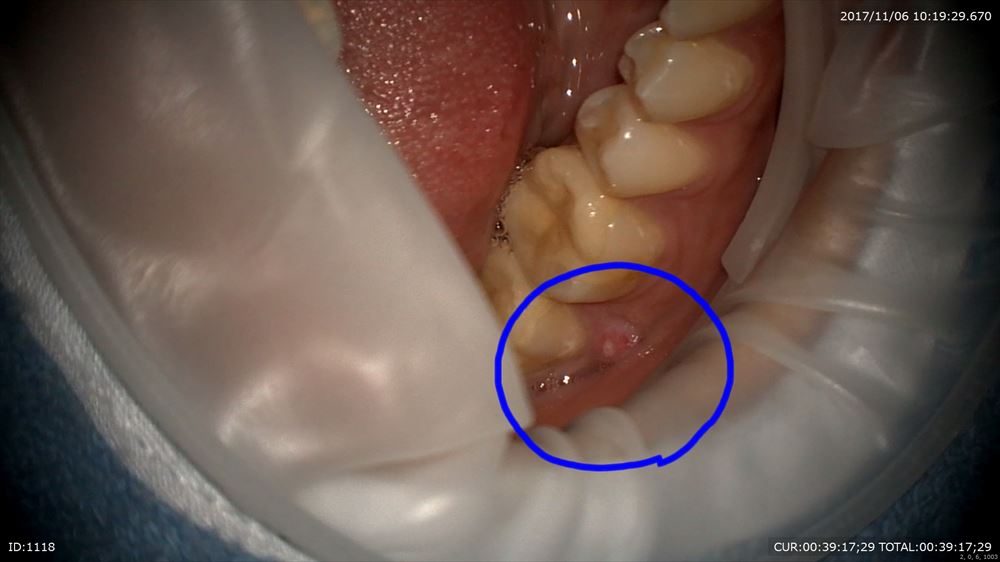

11月の初診時

右下の歯茎から膿が出ていました。

右下6.7に根尖性歯周炎。7番の近心は大きな透過像。6番の近心根は狭窄している。。。。難症例です。